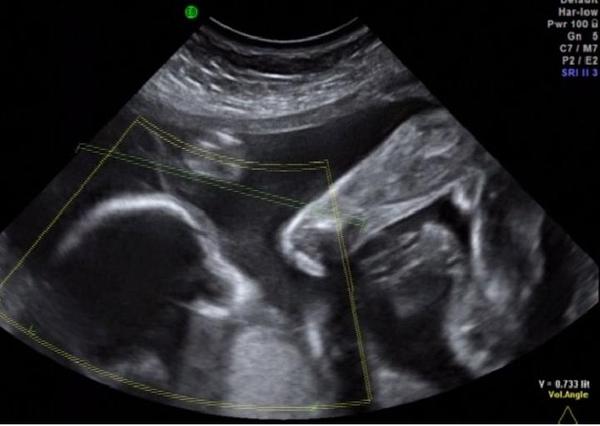

Ahoj, holky, jen hlásím, že holčička potvrzena. Včera jsme byli an 4D utz a bylo to hezky videt 🙂

Ahoj holky,tak já jsem se nedávno přidala fotku,a,ted na stopro potvrzuji,že čekáme holčičku,dnes 4Dultrazvuk a hned na nás vykoukla ta malá buchtička😀 Takže všem tipujícím děkuji a at se každému splní to,co si přeje,ale nejvíc,nejvíc zdraví,to je základ!!:-* (Trvalo to,než se ukázala,ale pak už se vystavovala,že se smál i doktor,za to obličejík víc skrývala🙂)